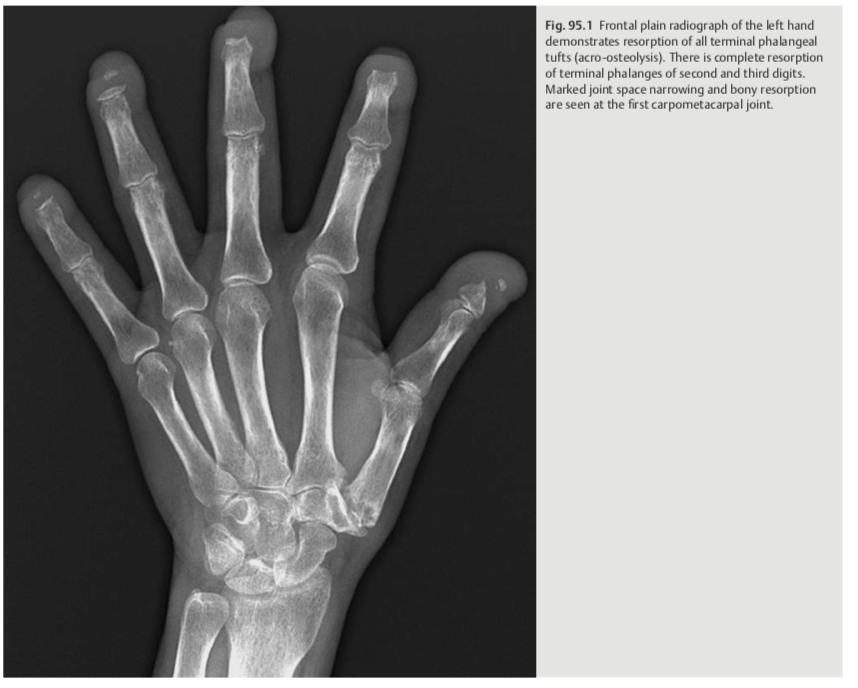

A 49-year-old woman with chronic bilateral hand pain and

ulcerations

Acro-osteolysis: